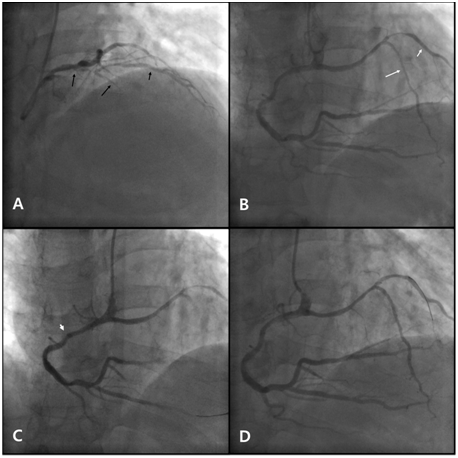

Figure 1 Coronary angiography and percutaneous coronary intervention.

1. Short LAD (long black arrow) originating from the LMCA, giving rise to the D1 (short black arrow). There is significant stenosis in the proximal portion of the short LAD and the proximal portion of the D1.

2. Long LAD (long white arrow) originating from the proximal RCA, coursing left, then turning downwards to the apex, giving rise to the D2 (long white arrow). There is significant stenosis of the distal RCA, the proximal PDA, the mid portion of the long LAD and the proximal portion of the D2.

3. Deep engagement (arrowhead) with a 6 Fr MP guiding catheter to deliver stents to the distal RCA.

4. Balloon angioplasty with a 6 Fr JR 4.0 guiding catheter at the mid portion of the long LAD and the proximal portion of the D2.

LAD: Left Anterior Descending Artery; LMCA: Left Main Coronary Artery; D1: First Diagonal Artery; RCA: Right Coronary Artery; PDA: Posterior Descending Artery; D2: Second Diagonal Artery; 6 Fr: 6 French; MP: Multipurpose; JR: Judkins Right.